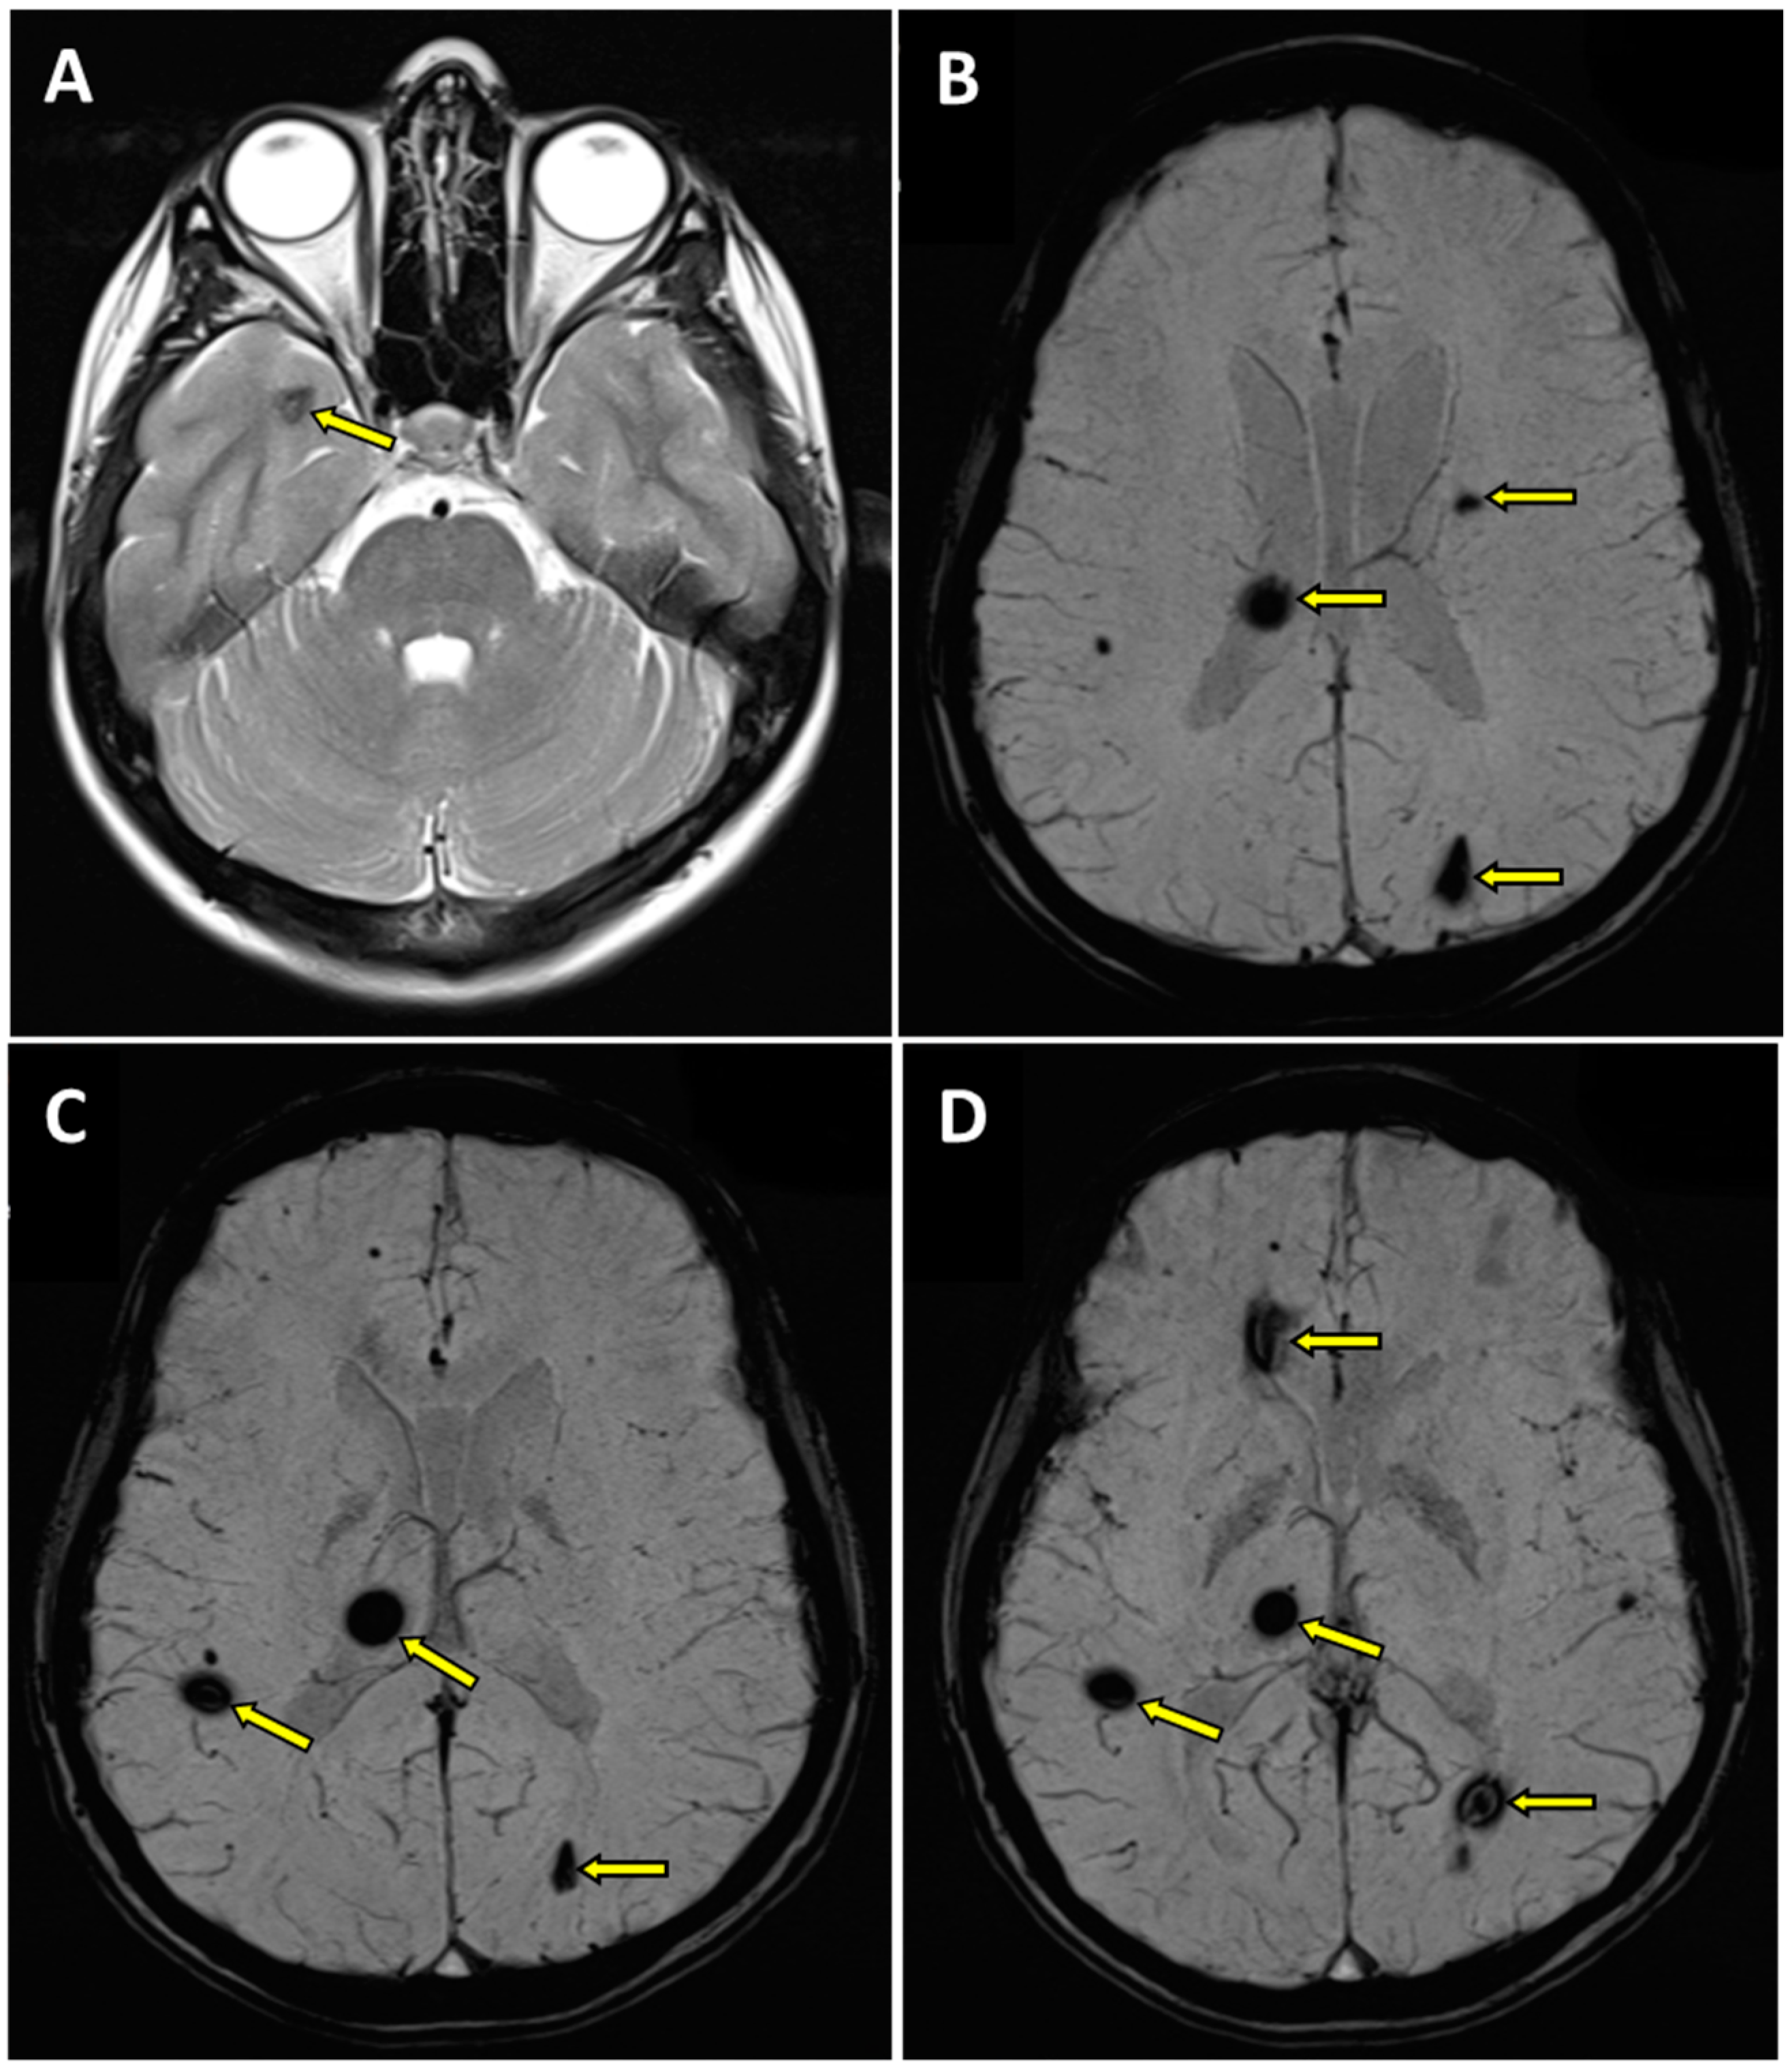

2. A Case Report

- -

- within the right thalamus (transverse dimensions of approx. 6 × 3.5 mm), with hemosiderin deposits,

- at the fronto-parietal junction on the right side in the subcortical location (transverse dimensions of approx. 3 × 5 mm),

- in the semioval center on the left side (transverse dimensions of approx. 7 × 4 mm),

- within the left occipital lobe (transverse dimensions of approx. 10 × 6 mm),

- in the right temporal lobe (transverse dimensions of approx. 7 × 3 mm and approx. 8 × 5 mm),

- in the area of the right frontal lobe (transverse dimensions of approx. 10 × 6 mm).